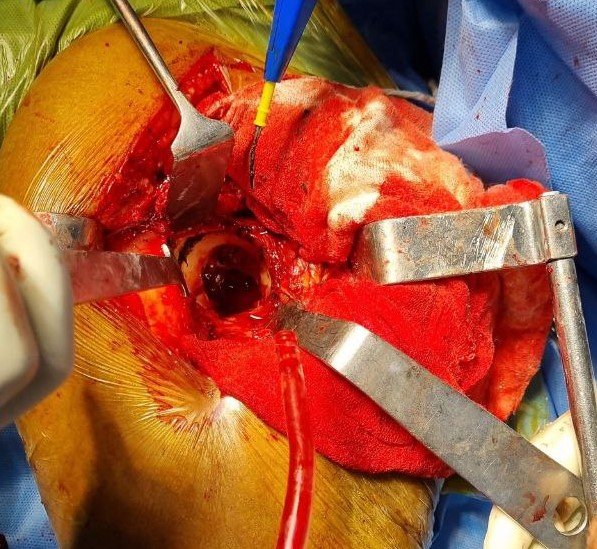

Garden Type IV Fracture Neck of Femur

Intra-Op (Photos)